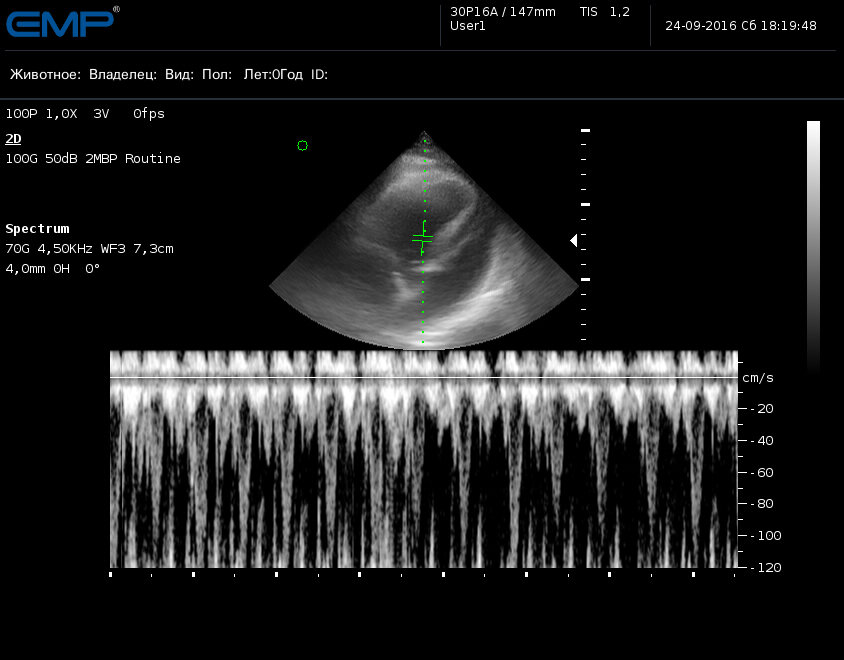

Импульсно-волновая допплерограмма транспульмонального потока, выполняется из правой парастернальной позиции на уровне аортального клапана, строб перед отверстием пульмонального клапана

Импульсно-волновая допплерограмма трансаортального потока, выполняется из левой апикостернальной 5-камерной позиции, строб выставлен перед аортальным клапаном

Стандартное ультразвуковое исследование сердца включает множество методик, такие как: 2D сканирование полостей сердца, исследование глобальных параметров функции сердца в М-режиме, цветное допплеровское картирование всех потоков, исследование локальных параметров миокарда тканевым допплеровским методом, построение профилей потоков через все клапана и выносящие/приносящие тракты желудочков и т.д.